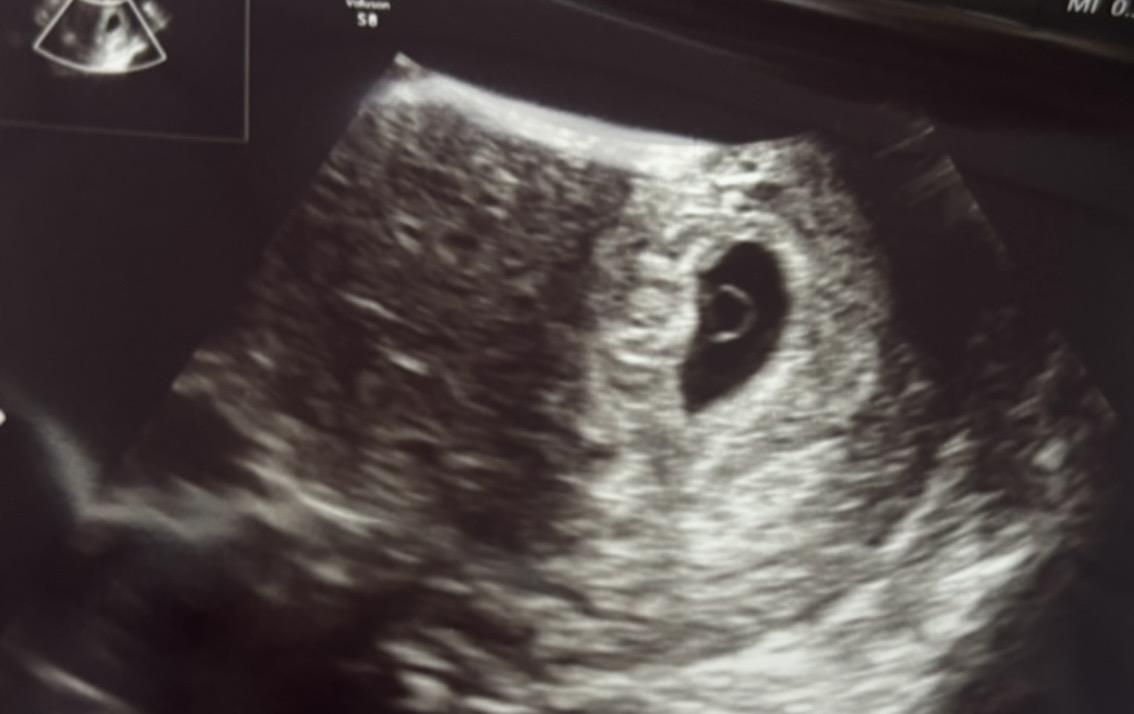

エコー写真はこちら。

エコー写真(10週0日)

手足が生えてきました(笑)

か、かわいい、、。

写真だと分からないですが、手がぴくぴく動いていました。

まだまだ体の形は出来上がっていないですが、どことなく人の形になってきてますよね!!

愛おしい、、